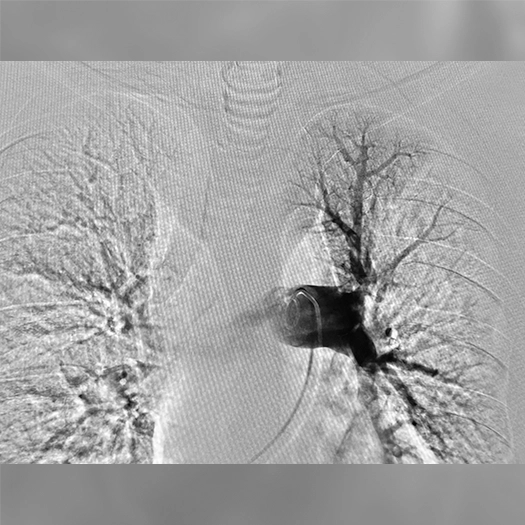

Pulmonary Embolism Cases